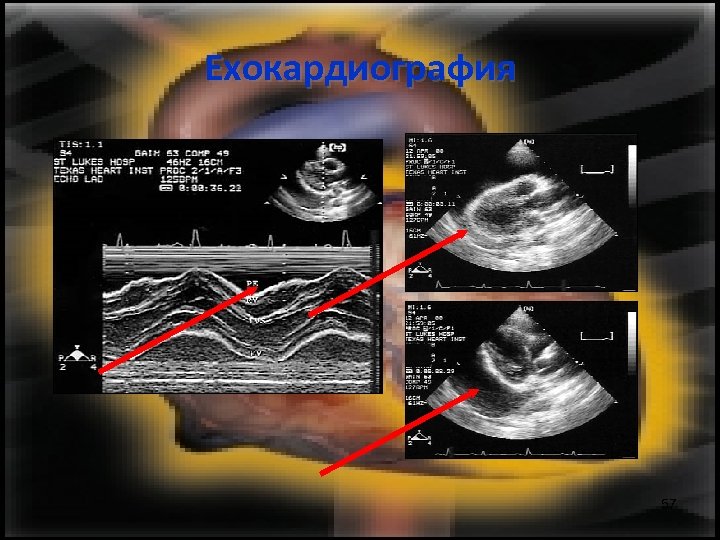

Ехокардиография Може да се оцени: • Кинетиката на сърдечния мускул • Количеството на излива 56

Ехокардиография 57